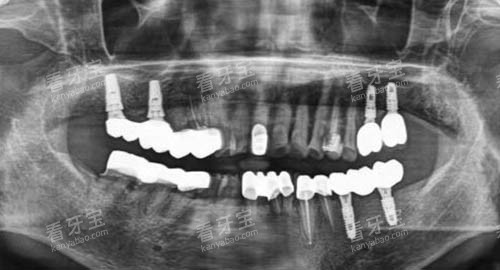

在种植牙方面,郑州植得口腔医院的种植导航系统是一大特色。

该系统利用计算机辅助设计和制造技术,结合患者的口腔 CT 数据,能够更好地规划种植体的位置、方向和深度。

在手术过程中,医生可以根据导航系统的指引,更加比较准地进行种植操作,减少手术创伤,缩短手术时间,提高种植成功概率。

同时,种植导航系统还可以模拟种植后的结果,让患者在手术前就能够直观地看到自己牙齿修复后的样子,增强患者的治疗信心。